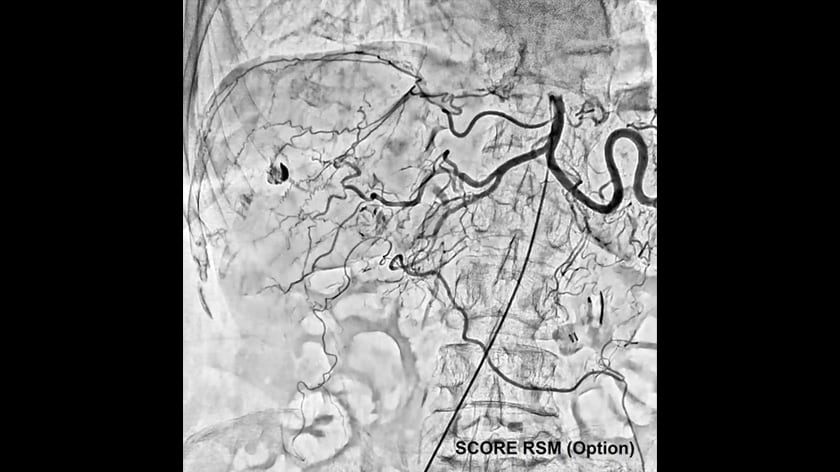

- Crossover Angiography System - Trinias series with SCORE Opera

Crossover Angiography SystemTrinias series

with SCORE Opera

The Trinias series with SCORE Opera is a Crossover Angiography System developed to provide solutions for the evolving challenges in medical treatment centers. This system is designed based on three core principles: ALARA (As Low As Reasonably Achievable) Design, Lean Design, and Sustainable Design.